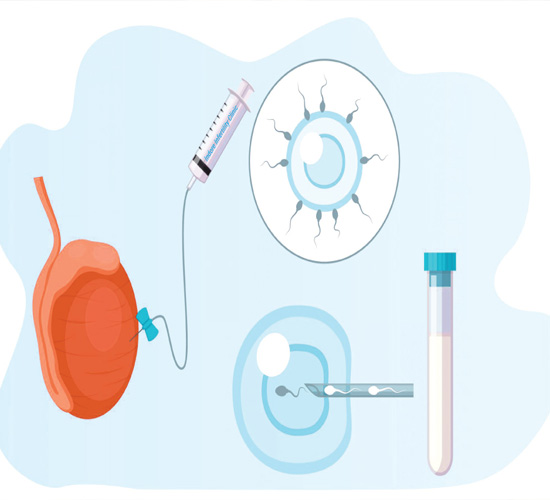

IVF Treatment

IVF helps couples conceive by combining eggs and sperm in a lab for fertilization, offering hope for those facing infertility challenges.

ICSI

ICSI is an advanced IVF technique where a single healthy sperm is directly injected into an egg, improving fertilization success rates.

IUI

IUI is a simple, non-invasive fertility treatment where processed sperm is directly placed into the uterus, increasing the chances of conception.